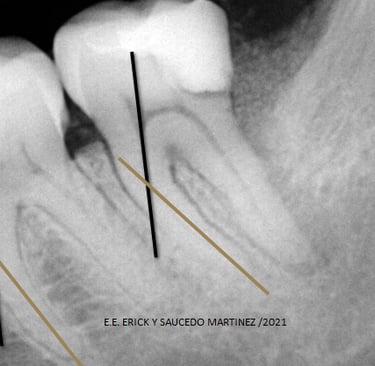

En 325 raíces analizadas radiográficamente, medidas por el método de Schneider la prevalencia de curvatura encontrada en este estudio es la siguiente:

Más del 70% de las raíces mesiales de los molares inferiores permanentes presentan un grado de curvatura mesiodistal severa, una cuarta parte de ellos presento curvatura moderada, siendo una mínima cantidad los casos observados con curvatura leve.

Existe una diferencia de 15.6% en incidencia de casos con curvatura severa reportados en pacientes mexicanos comparado con los pacientes extranjeros en las raíces mesiales de primeros molares inferiores.

En los casos analizados de curvaturas moderadas en dichos molares, se observó que los pacientes extranjeros tienen una mayor incidencia de casos reportados con una diferencia del 15.53% en comparación con los mexicanos.